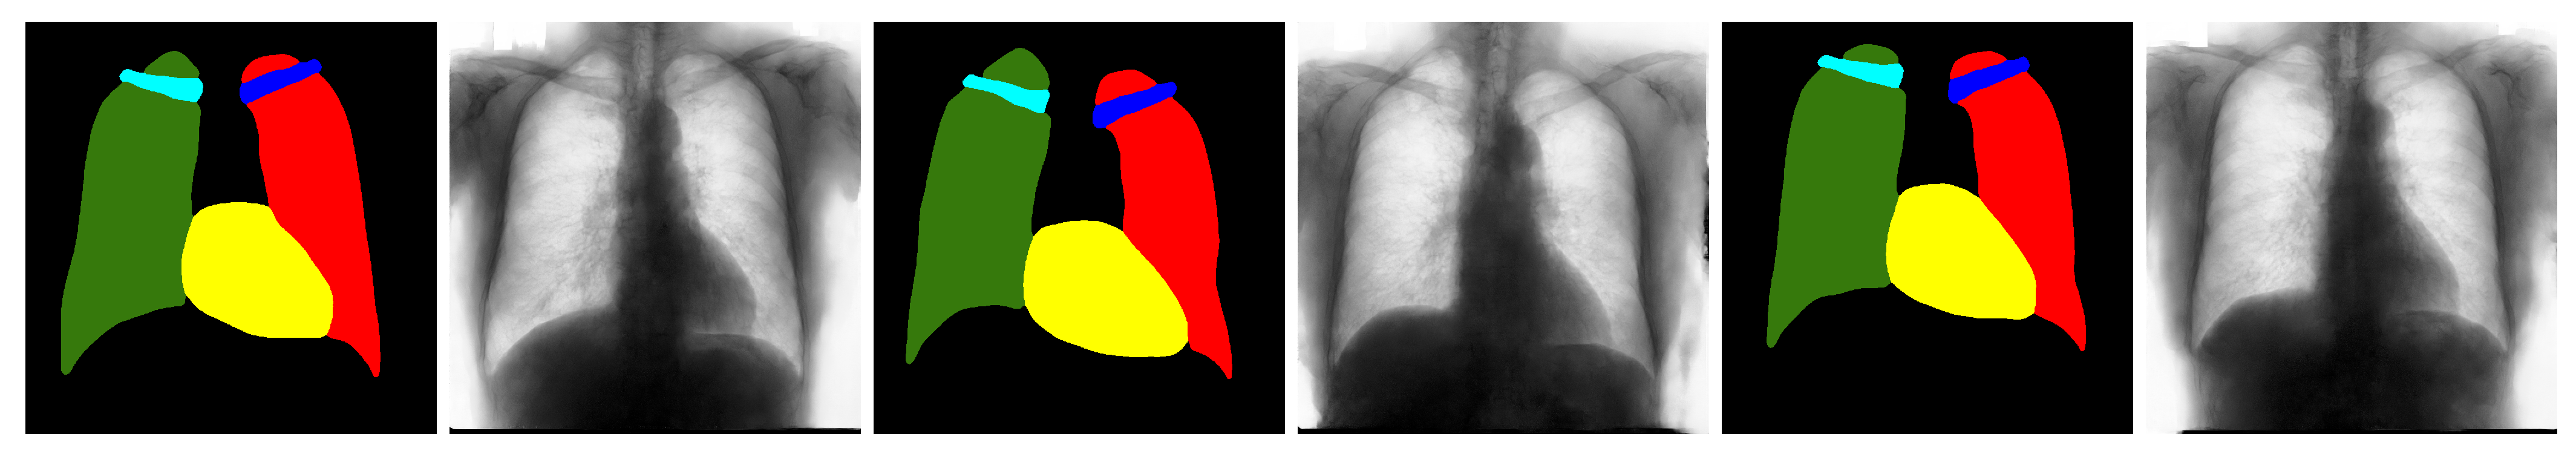

4.4. Qualitative Results